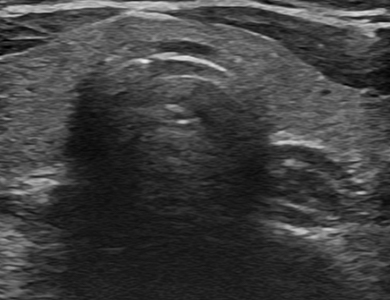

ÃÊÀ½ÆÄ »çÁø

Á¤»ó °©»ó¼± ÇùºÎ

img